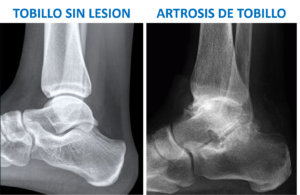

Diagnóstico de la artrosis de tobillo

En casos avanzados, una radiografía con carga de la pierna permite confirmar la presencia de artrosis y evaluar desviaciones en el tobillo. En etapas iniciales, la resonancia magnética es clave para detectar daños en el cartílago, especialmente en la cúpula del astrágalo. Un diagnóstico y tratamiento tempranos son esenciales para prevenir las graves consecuencias de un deterioro cartilaginoso no detectado.